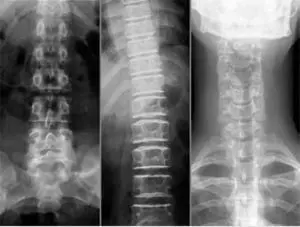

Рентген хребта – це спосіб візуалізації тіл хребців, який допоможе лікарю зорієнтуватися в в анатомії хребетного стовпа, побачити відхилення вродженого або набутого характеру. У цих випадках, для діагностики стану і, в наслідку, ефективного лікування, лікарі призначають рентгенографію хребта, який ділиться на 5 відділів:

Для кожного з відділів характерні свої симптоми і патології. Але на рентгенівському знімку не будуть видні м’які тканини і кровоносні судини. Даний вид дослідження призначений тільки для візуалізації кісткової тканини хребців. Для дослідження кожного з цих відділів розроблені методики рентгенографії.

Лікар-рентгенолог на рентген-знімку хребта бачить:

- стан тіл хребців – в нормі не повинно бути тріщин, зсувів, зміни висоти між хребцями, змін форми тіл

- відсутність або наявність патології в міжхребцевих дисках

- місця прикріплення до хребців ребер

- з’єднання хребта з тазом